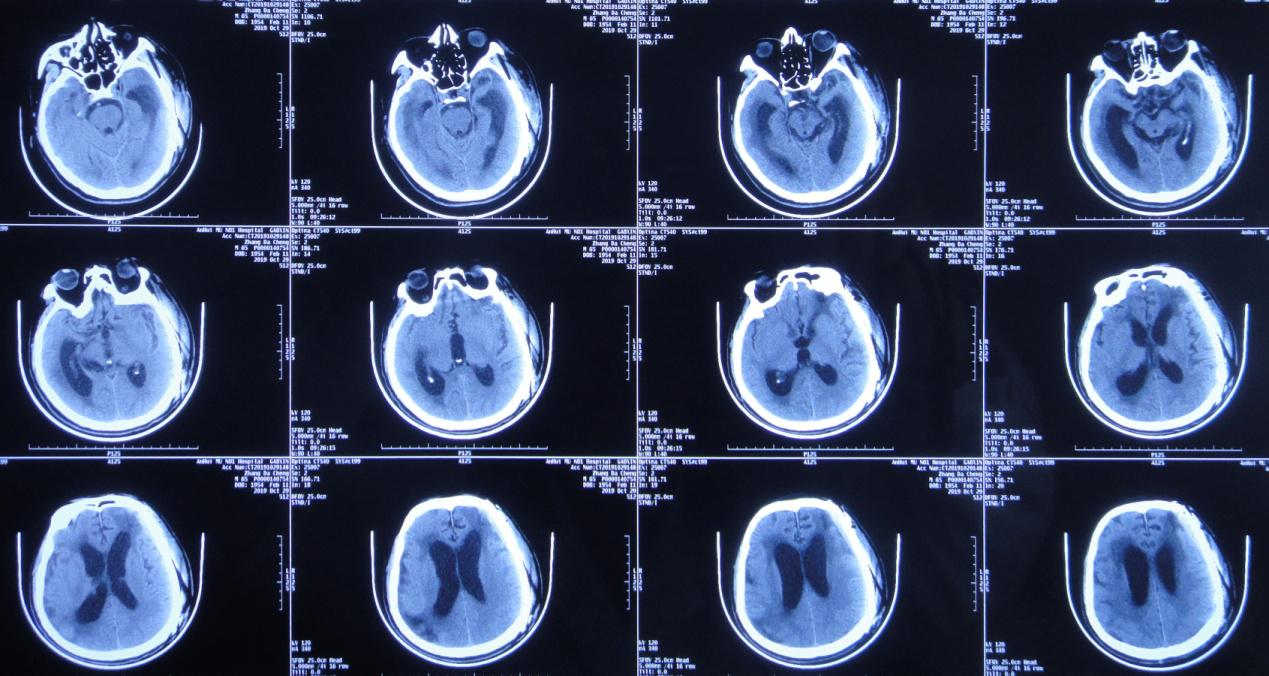

左颞叶血肿清除+去骨瓣减压术后第106天,即2019年 10月24日行颅骨修补术。

颅骨修补术后第5天即2019年 10月29日复查头颅CT( 图-7 )呈颅骨修补术后改变,脑室较前无变化。

图-7: 2019年10月29日术后头颅CT

颅骨修补术后第14天,即2019年 11月8日患者出现双下肢力量反而较前减退(注:本人观点最好不要先补颅骨),行走需1人搀扶,复查头颅CT( 图-8 )示脑室较前无明显变化(但双颞角较前稍扩大)。

图-8: 2019年11月8日头颅CT

医生嘱患者加强康复锻炼,但是双下肢力量反而更逐渐继续减退,且意识也加重,由原来清醒的状态又逐渐变为嗜睡。

患者意识进一步恶化,颅骨修补术后第34天,即2019年 11月28日,患者意识由嗜睡变为昏睡状态,复查头颅CT( 图-9 )示脑室较前稍增大,脑室周围水肿稍加重。

图-9: 2019年11月28日头颅CT

意识逐渐恶化脑室不断扩大,2019年12月4日行右侧脑室钻孔外引流术,术后当日复查头颅CT( 图-10 )呈脑室钻孔外引流术后改变。

图-10: 2019年12月4日术后头颅CT